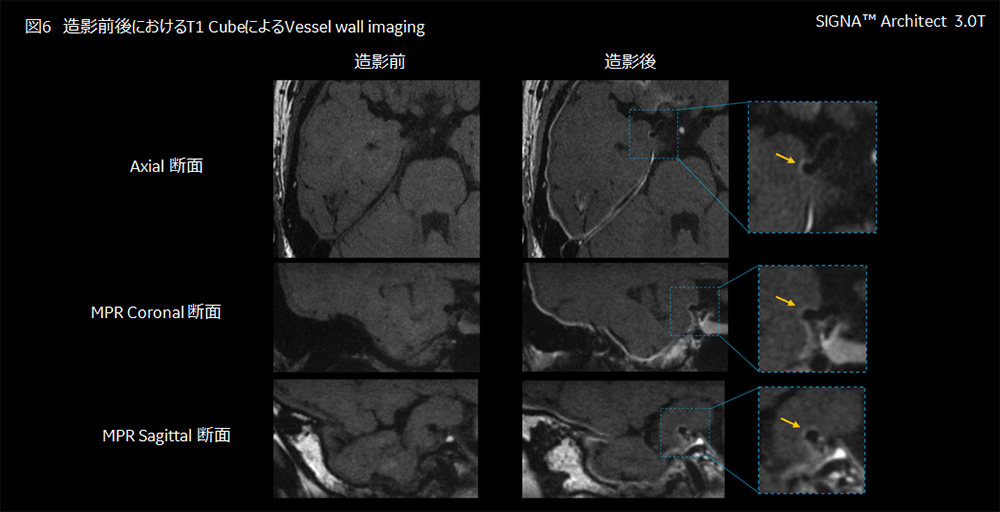

当初、同側に動脈瘤を認めるものの、くも膜下腔に血腫は無いためSAHではなく右急性硬膜下血腫と診断され、保存治療のため経過入院の方針となった。しかし、外傷の既往なく非典型的な硬膜下出血のため、くも膜下腔に血腫のないSAHの可能性もあり造影MRIにて評価することとなった。Case1と同様に3.0T装置にて、造影剤投与の前後でT1 Cubeを用いたVessel wall imagingの撮像を行った。造影MRIにて右内頸-後交通動脈瘤の壁に増強効果が認められ、血腫は後方のテント上を回り脳表へ流れていることが確認された(図6)。破裂点がくも膜下に顔を出しており、くも膜下腔を介さず直接硬膜下血腫になった右内頸-後交通動脈瘤破裂によるSAHと診断された。その後、クリッピング術が施行され、術後経過は良好で、新たな神経症状なく退院された。